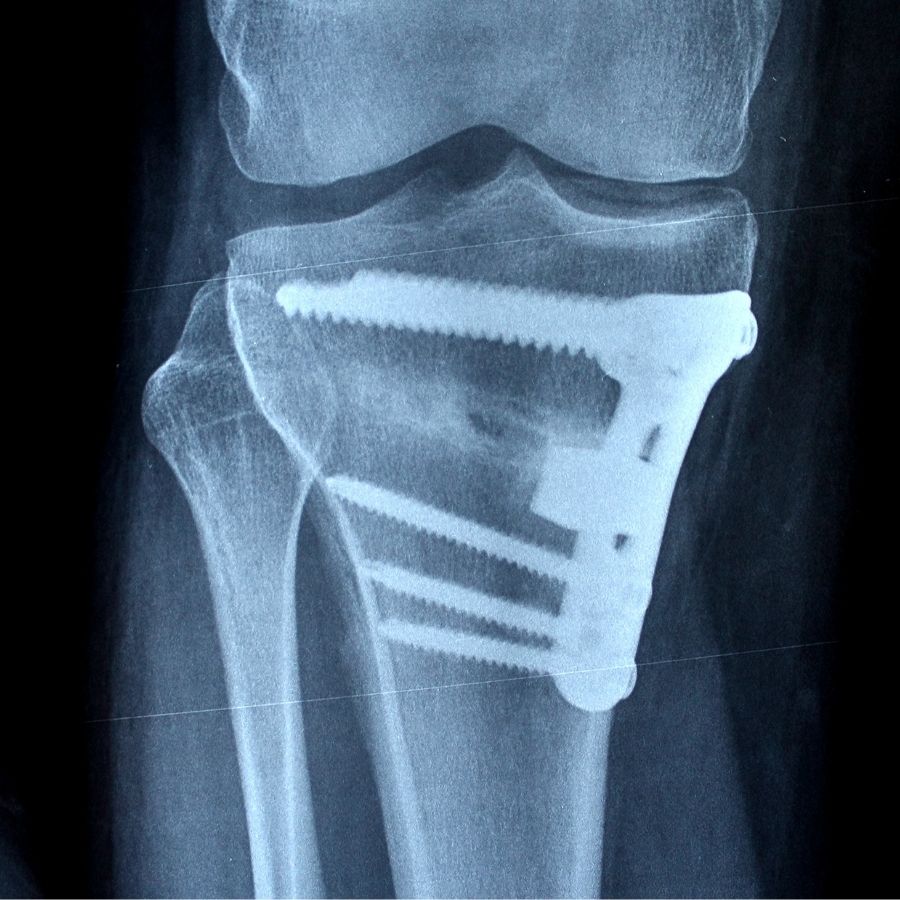

È un esperto nella Chirurgia Protesica del ginocchio e dell’anca, nelle tecniche di Artroscopia del Ginocchio, nella ricostruzione del legamento crociato anteriore e nelle plastiche di rinforzo esterne per le instabilità rotazionali del ginocchio. Altri interventi da lui eseguiti con frequenza sono il trattamento chirurgico delle fratture del piatto tibiale e del femore, trattamenti chirurgici per la lussazione della rotula. Tra i suoi campi d’interesse ci sono anche la Chirurgia Mini-Invasiva e la Traumatologia Sportiva. Da qualche anno è interessato all’applicazione di PRP per il trattamento di malattie acute e croniche dei tendini e delle articolazioni. Attualmente è Chirurgo Ortopedico presso la Clinica Fornaca di Sessant, Dirigente Medico di I livello presso l’Ospedale Humanitas Gradenigo e svolge la libera professione presso il suo studio privato a Torino.

Il Navio , utilizzato dall’ortopedico durante un intervento chirurgico per impiantare una protesi al ginocchio, è un sistema robotico che aumenta la precisione e rende l’intervento chirurgico meno invasivo garantendo anche un allungamento della vita della protesi stessa.

Il sistema robotico Navio permette di posizionare la protesi del ginocchio in modo molto rapido e con una precisione difficilmente eguagliabile dalla mano del chirurgo, per quanto esperto.

Con l’ausilio del Sistema chirurgico Navio l’ortopedico potrà impiantare la protesi più idonea al tipo di lesione su cui si interviene, in quanto la protesi sarà scelta ad hoc in base al movimento del ginocchio ed alla specifica anatomia.

Il chirurgo avrà la possibilità di impiantare la protesi beneficiando di una pianificazione strumentale in tre dimensioni che, grazie al sistema Navio, permette non solo precisione accurata ma anche rapidità nell’esecuzione dell’intervento.

Con questo nuovo strumento computer-assistito il chirurgo trarrà il massimo vantaggio utilizzandolo sia per l’impianto di protesi totale che protesi monocompartimentale.